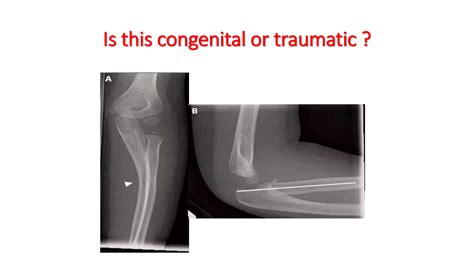

Diagnosis of Radial Head Subluxation

Diagnosing radial head subluxation typically involves a physical examination by a healthcare provider. The diagnosis is usually based on the child's history and symptoms. In some cases, an X-ray may be ordered to rule out other injuries, such as fractures. However, X-rays are not always necessary for diagnosing radial head subluxation.